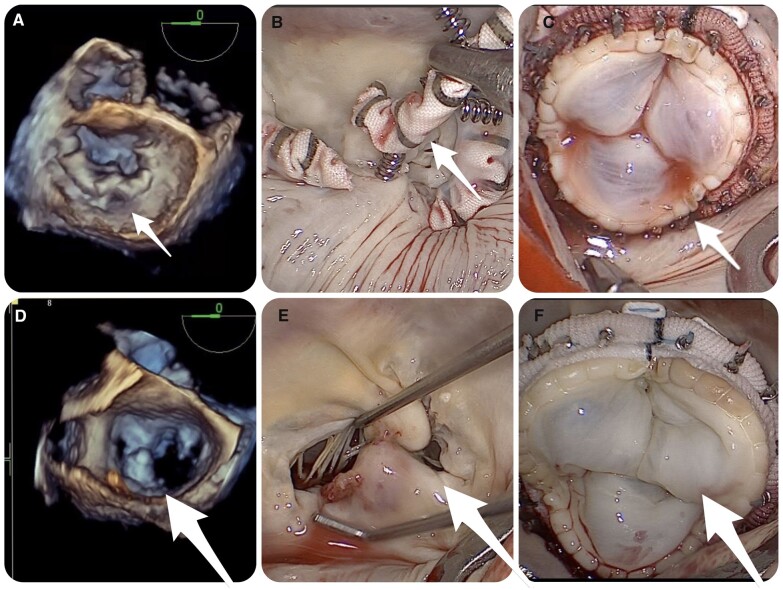

Objectives: Although clinical experience with transcatheter mitral valve interventions is rapidly increasing, there is still a lack of evidence regarding surgical treatment options for the management of recurrent mitral regurgitation (MR). This study provides guidance for a minimally invasive surgical approach following failed transcatheter mitral valve repair, which is based on the underlying mitral valve (MV) pathology and the type of intervention.

Methods: A total of 46 patients who underwent minimally invasive MV surgery due to recurrent or residual MR after transcatheter edge-to-edge repair or direct interventional annuloplasty between October 2014 and March 2021 were included.

Results: The median age of the patients was 78 [interquartile range, 71-82] years and the EuroSCORE II was 4.41 [interquartile range, 2.66-6.55]. At the index procedure, edge-to-edge repair had been performed in 45 (97.8%) patients and direct annuloplasty in 1 patient. All patients with functional MR at the index procedure (n = 36) underwent MV replacement. Of the patients with degenerative MR (n = 10), 5 patients were eligible for MV repair after removal of the MitraClip. The 1-year survival following surgical treatment was 81.3% and 75.0% in patients with functional and degenerative MR, respectively. No residual MR greater than mild during follow-up was observed in patients who underwent MV repair.

Conclusions: Minimally invasive surgery following failed transcatheter mitral valve repair is feasible and safe, with promising midterm survival. The surgical management should be tailored to the underlying valve pathology at the index procedure, the extent of damage of the MV leaflets and the type of previous intervention.